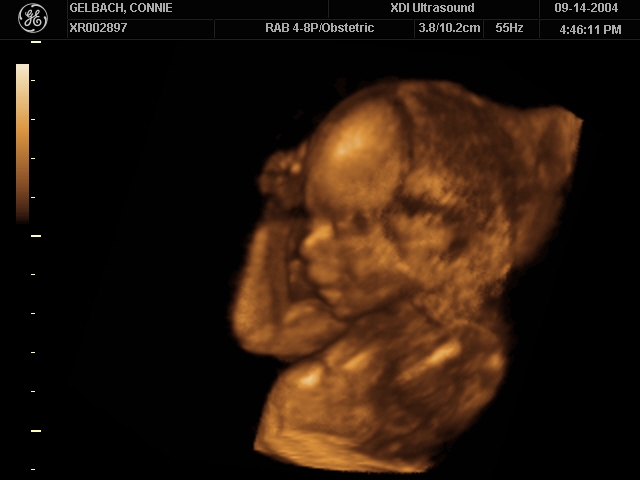

Sonograms